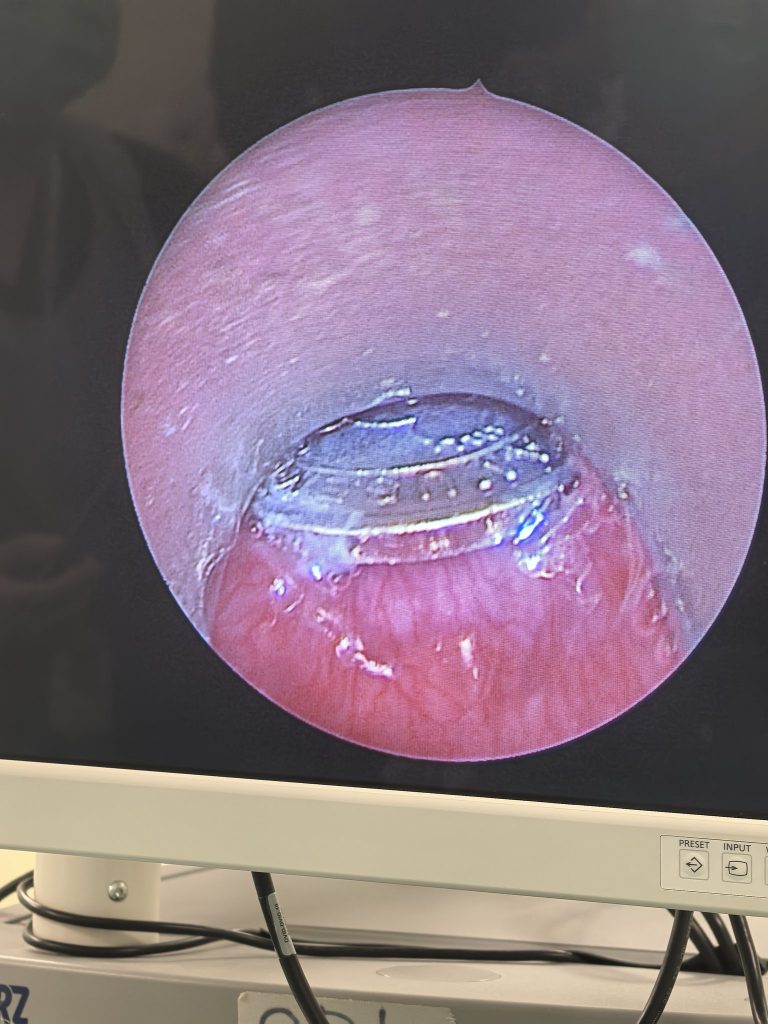

However, during the procedure, he was puzzled to discover that the foreign object didn’t look like a coin.

The realisation that it was an arcade token took him by surprise.

This was the first time he’d encountered a case like this, he said.

Thankfully, the surgery went smoothly, he added.